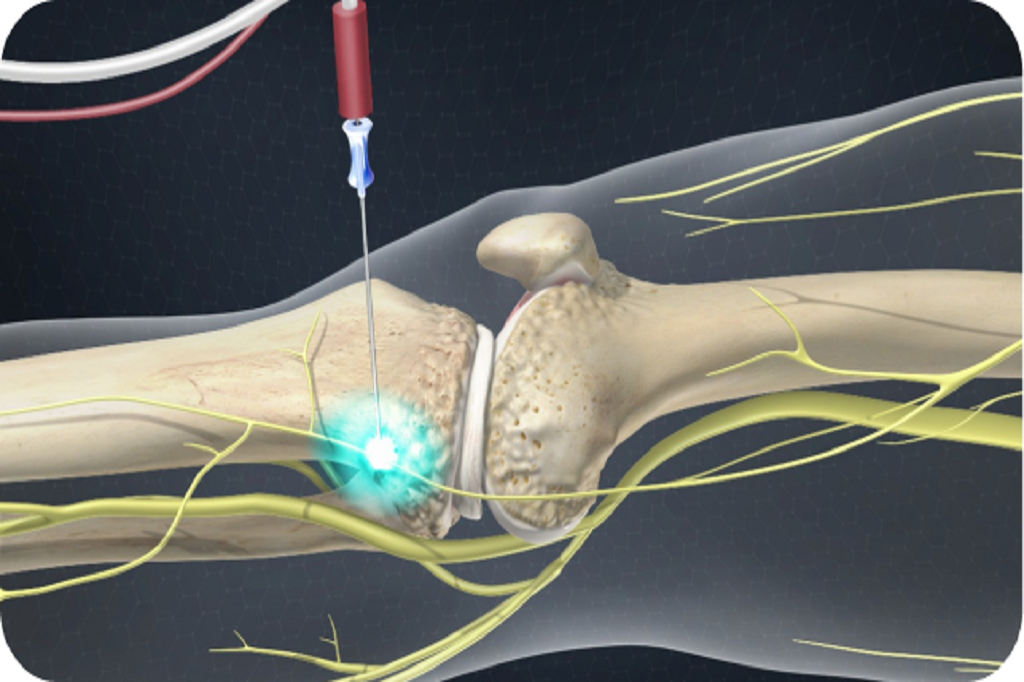

A two-step process. First, a diagnostic nerve block identifies the pain source.If successful, Radiofrequency Ablation is used to provide long-lasting relief.

For nerve-related knee pain after trauma or surgery.